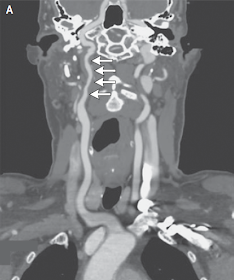

El procedimiento de diagnóstico fue angiografía por TC de cabeza y cuello. Las imágenes curvadas y reconstruidas  mostraron un estrechamiento irregular de la arteria carótida interna derecha cervical que se extiende desde cerca de su origen hasta la base del cráneo (Figura 1A y 1B).

Figura 1. Imágenes curvadas y reconstruidas de una angiografía por TC de la cabeza y el cuello.

Las imágenes se reconstruyeron   para visualizar la extensión completa de las arterias carótidas comunes e internas  derecha  (Panel A) e izquierda (Panel B). Las flechas delinean los segmentos cervicales de las arterias carótidas internas. Hay un estrechamiento irregular de la arteria carótida interna derecha en comparación con la izquierda.